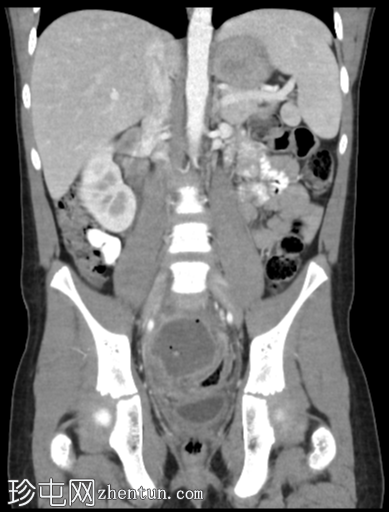

冠状位增强扫描(门静脉期)

3.png

右下腹可见强化且环周增厚的阑尾(轴位、矢状位、冠状位),周围阑尾周围脂肪组织呈条索状改变。阑尾尖端与一个复杂的厚壁积液相通,积液内可见气液平面。积液内可见下垂的钙化灶。积液导致增厚的直肠乙状结肠向左侧移位。

本例为阑尾穿孔继发盆腔脓肿。